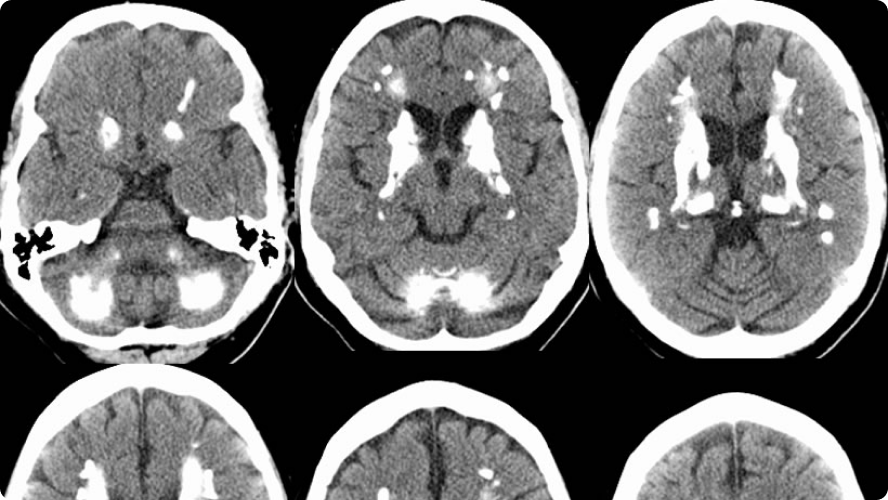

CASE 6- FAHR’S DISEASE

DIAGNOSIS

Findings

Near symmetric patchy calcifications are seen in bilateral cerebral and cerebellar hemispheres including:

- Bilateral basal ganglia

- Thalami

- Dentate nuclei

- Bilateral corona radiata.

Discussions

Fahr’s disease, also known as bilateral striatopallidodentatecalcinosis, is characterized by abnormal vascular calcium deposition, particularly in the basal ganglia, cerebellar dentate nucleiand white matterwith subsequent atrophy. It typically presentsin 40 to 60 years of age

- Primary: equivalent to familial cerebral ferrocalcinosisor primary familial brain calcification (now the preferred term), with no underlying other cause. Its usually autosomal dominant.

- Secondary: due to an underlying metabolic, infective or other cause

The condition that has been closely described with diffuse, bilateral, symmetric striopallidodentatecalcinosis is primary hypoparathyroidism,lupus, tuberous sclerosis, Alzheimer’s disease, myotonic muscular dystrophy and mitochondrial encephalopathies. When there is no explainable cause for striopallidodentatecalcinosis, the condition is termed as Fahr’s disease.

The treatment of Fahr’s diseaseis directed to the identifiable cause especially hypoparathyroidism. In other cases, symptomatic or conservative therapy with clinical follow-up is the rule. Prognosis is variable, cannot be predicted and is unrelated to the extent of calcification. Death usually occurs secondary to neurological deterioration.